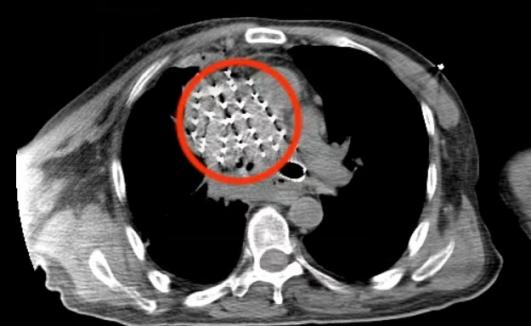

CT下碘125粒子植入